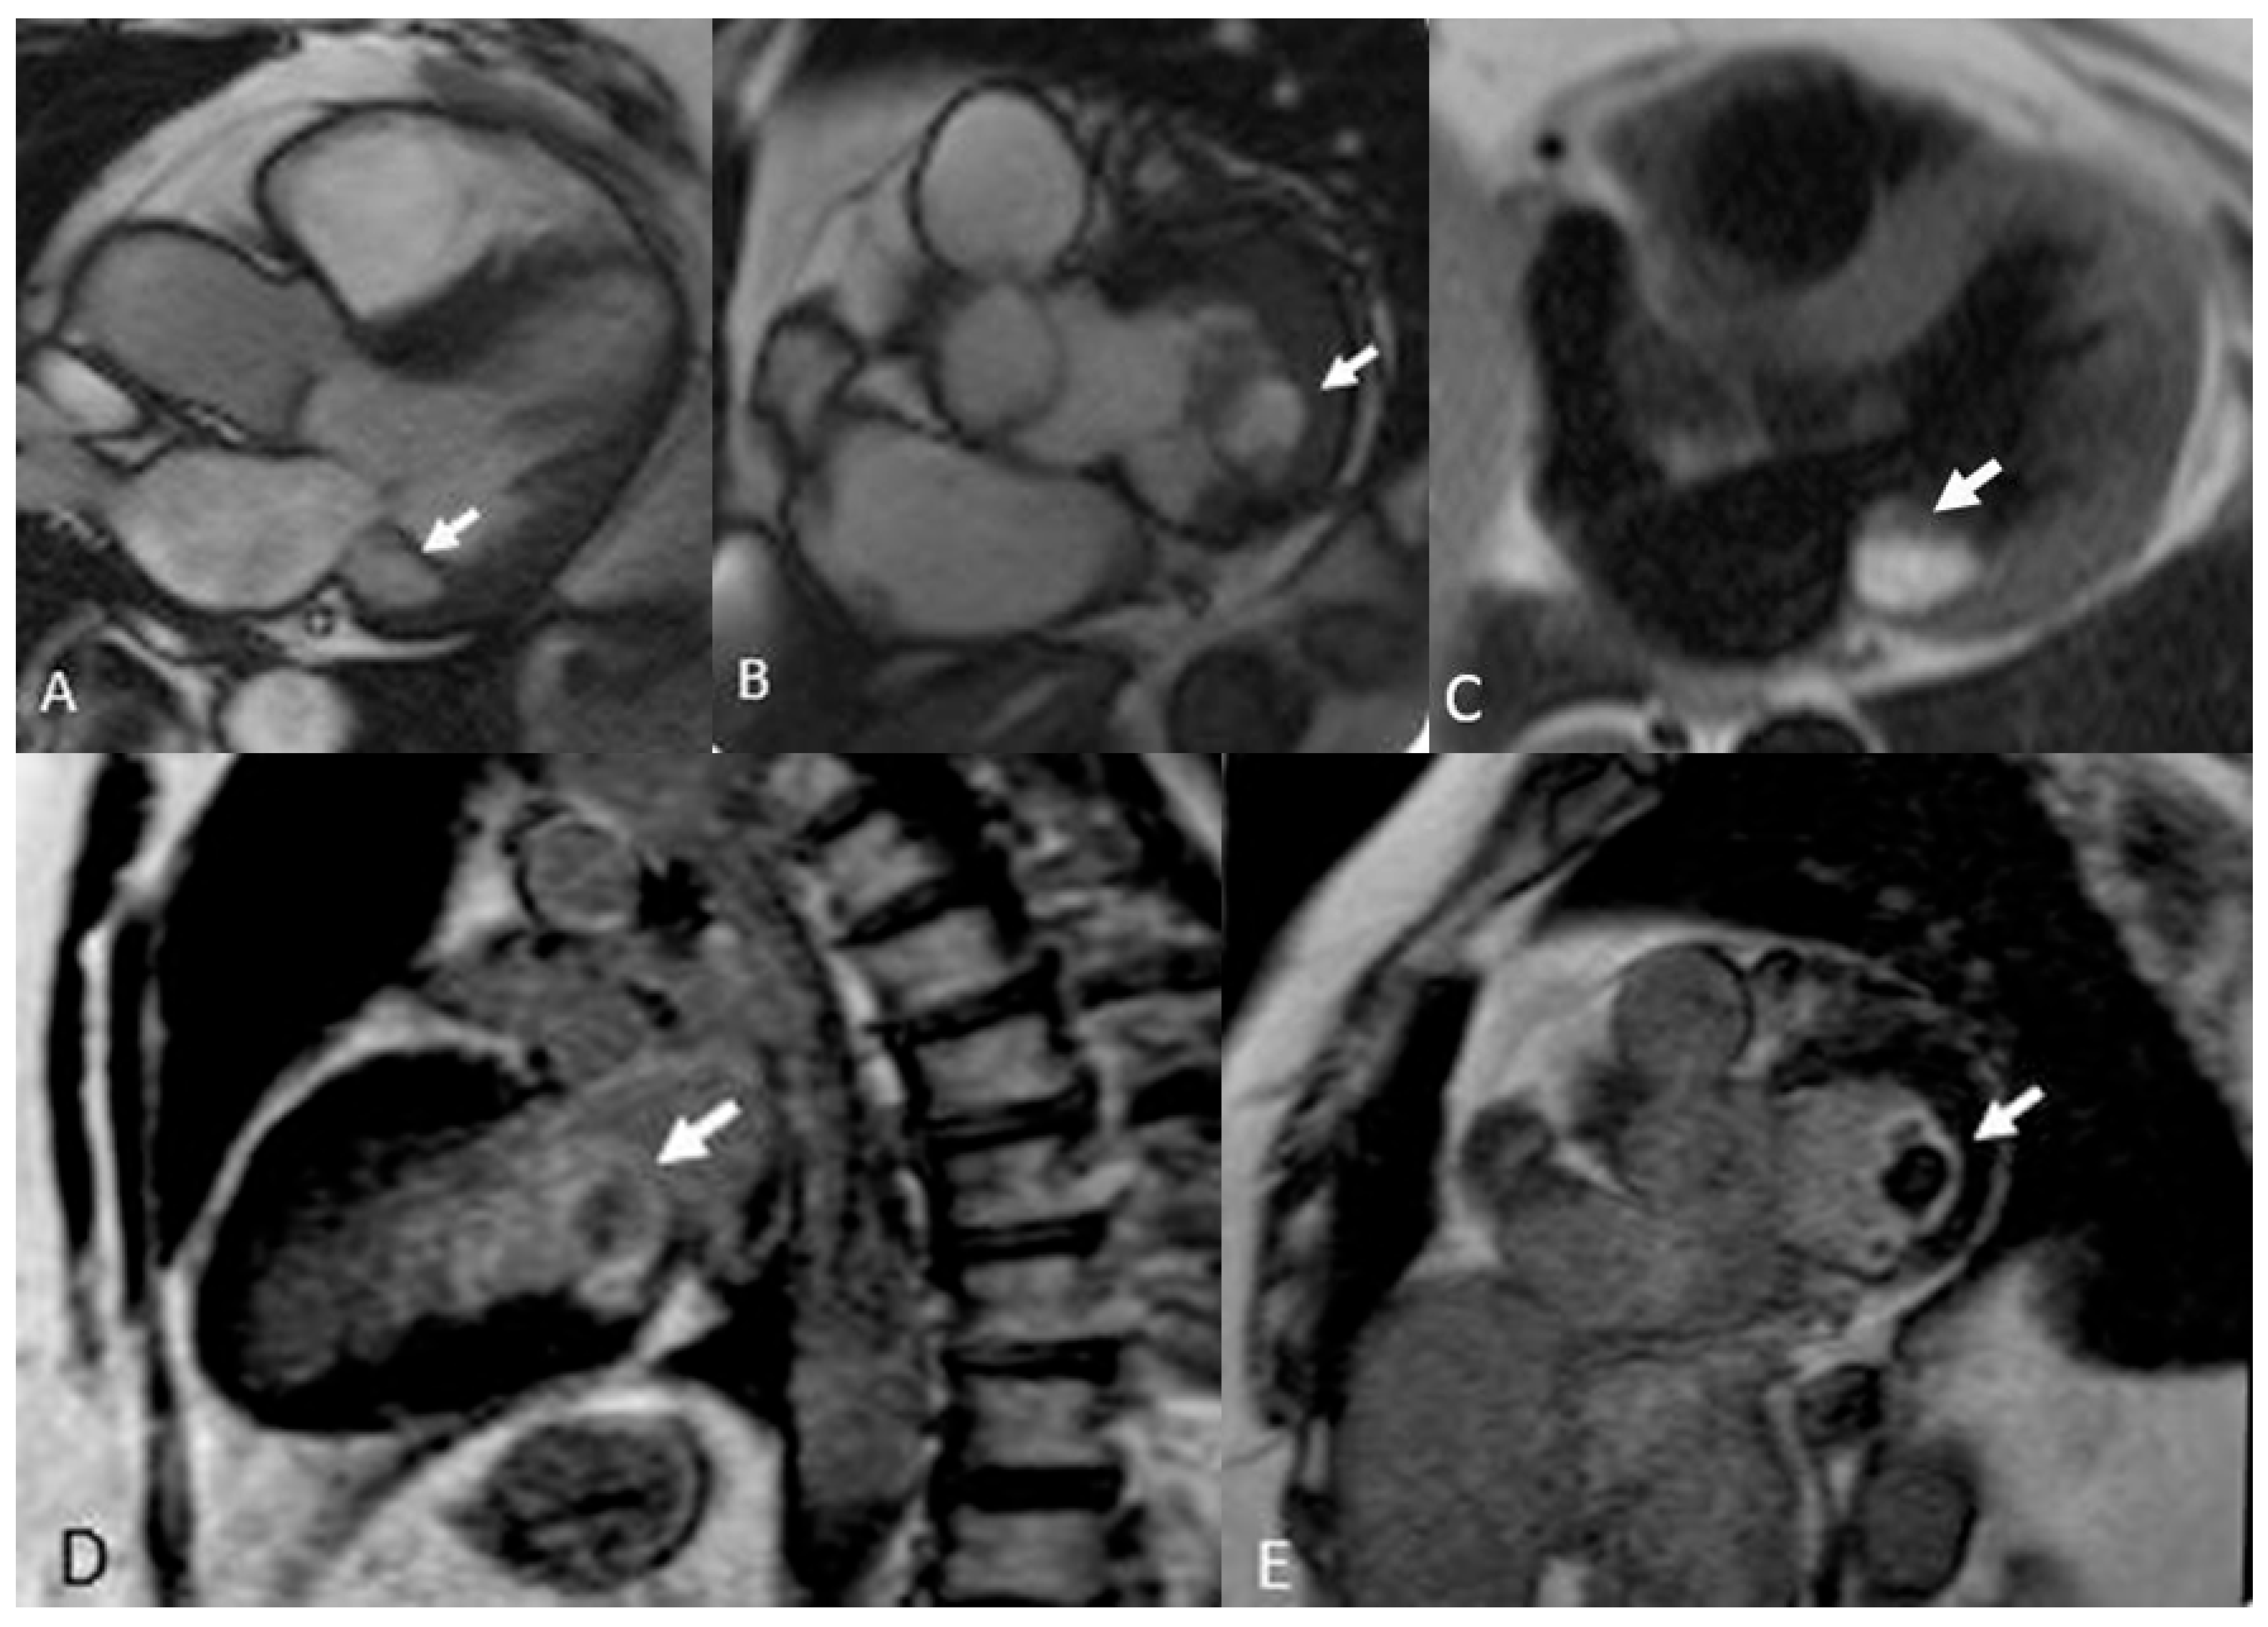

Cardiac metastases are secondary tumors involving the heart, representing the spread of tumors via the lymphatic and blood vessels. Although rare, cardiac metastases are much more common than primary cardiac tumors, with a ratio of about 30:1 and a frequency of 18% in oncological patients. The most common primary tumors that metastasize to the heart include lung cancer, breast cancer, renal cancer, ovarian cancer, pleural mesothelioma, malignant melanoma (Figure 13ta), chordoma (Figure 14) and lymphoma [52,53].

MRI usually shows hypointense images in T1 and hyperintense in T2, with avid contrast enhancement after administration. Malignant melanoma shows T1 hyperintensity due to the paramagnetic properties of melanin, low intensity in , T2 images and heterogeneous appearance on LGE imaging [54]. These characteristics allow for a specific diagnosis without the need for a biopsy [3].

Figure 14. Melanoma metastasis (red arrows). 14 x 10 mm nodular lesion on the inferior wall of the right atrium (A, B) characterized by hyperintensity in T1w-black blood 4ch (C), inhomogeneous enhancement in short-axis perfusion sequences (D) and weak enhancement in T1w-fat sat after 20 minutes (E). Positron emission tomography image in the short axis plane shows increased SUV (5.7) of the nodular lesion.